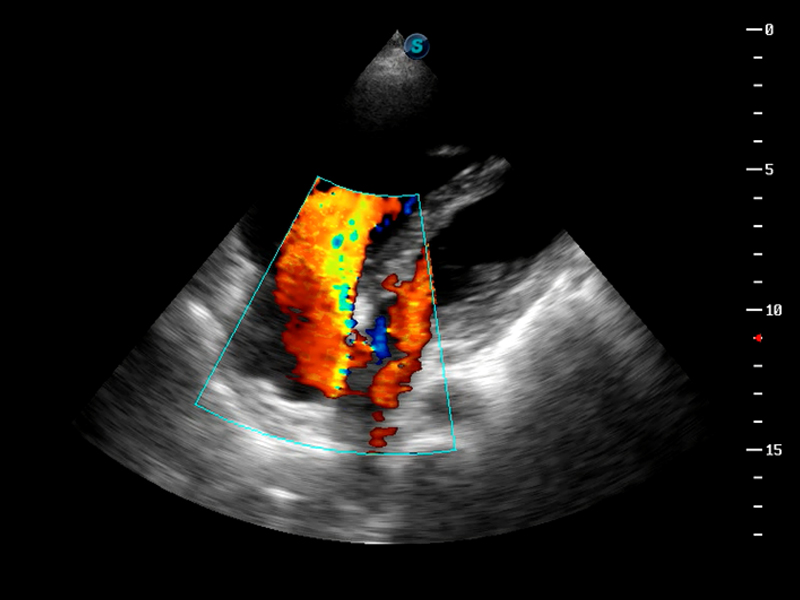

S9便携式彩色多普勒超声诊断仪是狗万官方网站研发的高端便携彩超设备,外观设计新颖、产品性能卓越。S9在便携超声领域采用了突破传统的触摸屏交互设计,并以先进的软件硬件技术和设计理念,为您带来清晰的图像质量、稳定的工作性能和便捷的操作体验。

TDI组织多普勒成像